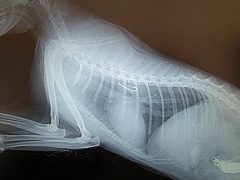

Katze mit verschlucktem Angelhaken